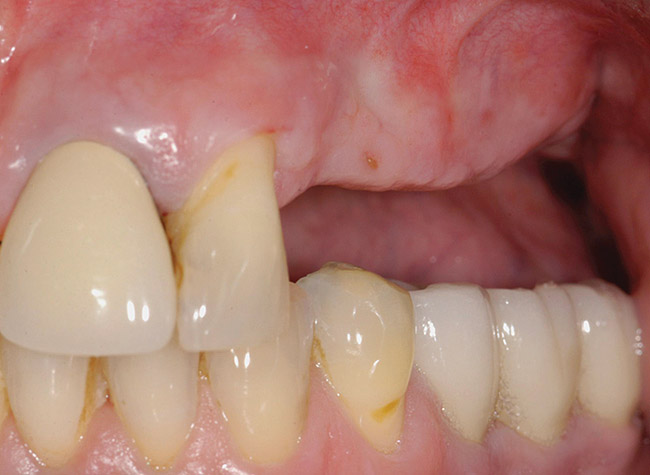

A 62-year-old woman was referred for fixed tooth replacement of the missing maxillary left cuspid, bicuspids, and first molar (Figure 11). Clinical and CBCT evaluation revealed an almost fully pneumatized maxillary left sinus along with alveolar width deficiency. The treatment plan called for a four-unit, implant-supported splinted fixed bridge. A left sinus augmentation along with a ridge split and interpositional bone graft consisting of rhBMP-2/ACS (INFUSE Bone Graft) and mineralized allograft (MinerOss) covered by a dense porous polyethylene mesh (Medpor®, Stryker, www.stryker.com) were done simultaneously (Figure 12, Figure 13 and Figure 14). Six months later, a follow-up CBCT revealed a well-incorporated graft with adequate bone volume and density for implant placement (Figure 15 and Figure 16). Final bridge fabrication followed 3 months later (Figure 17 and Figure 18).

Figure 11  Edentulous left posterior maxilla with alveolar ridge deficiency.

Figure 11